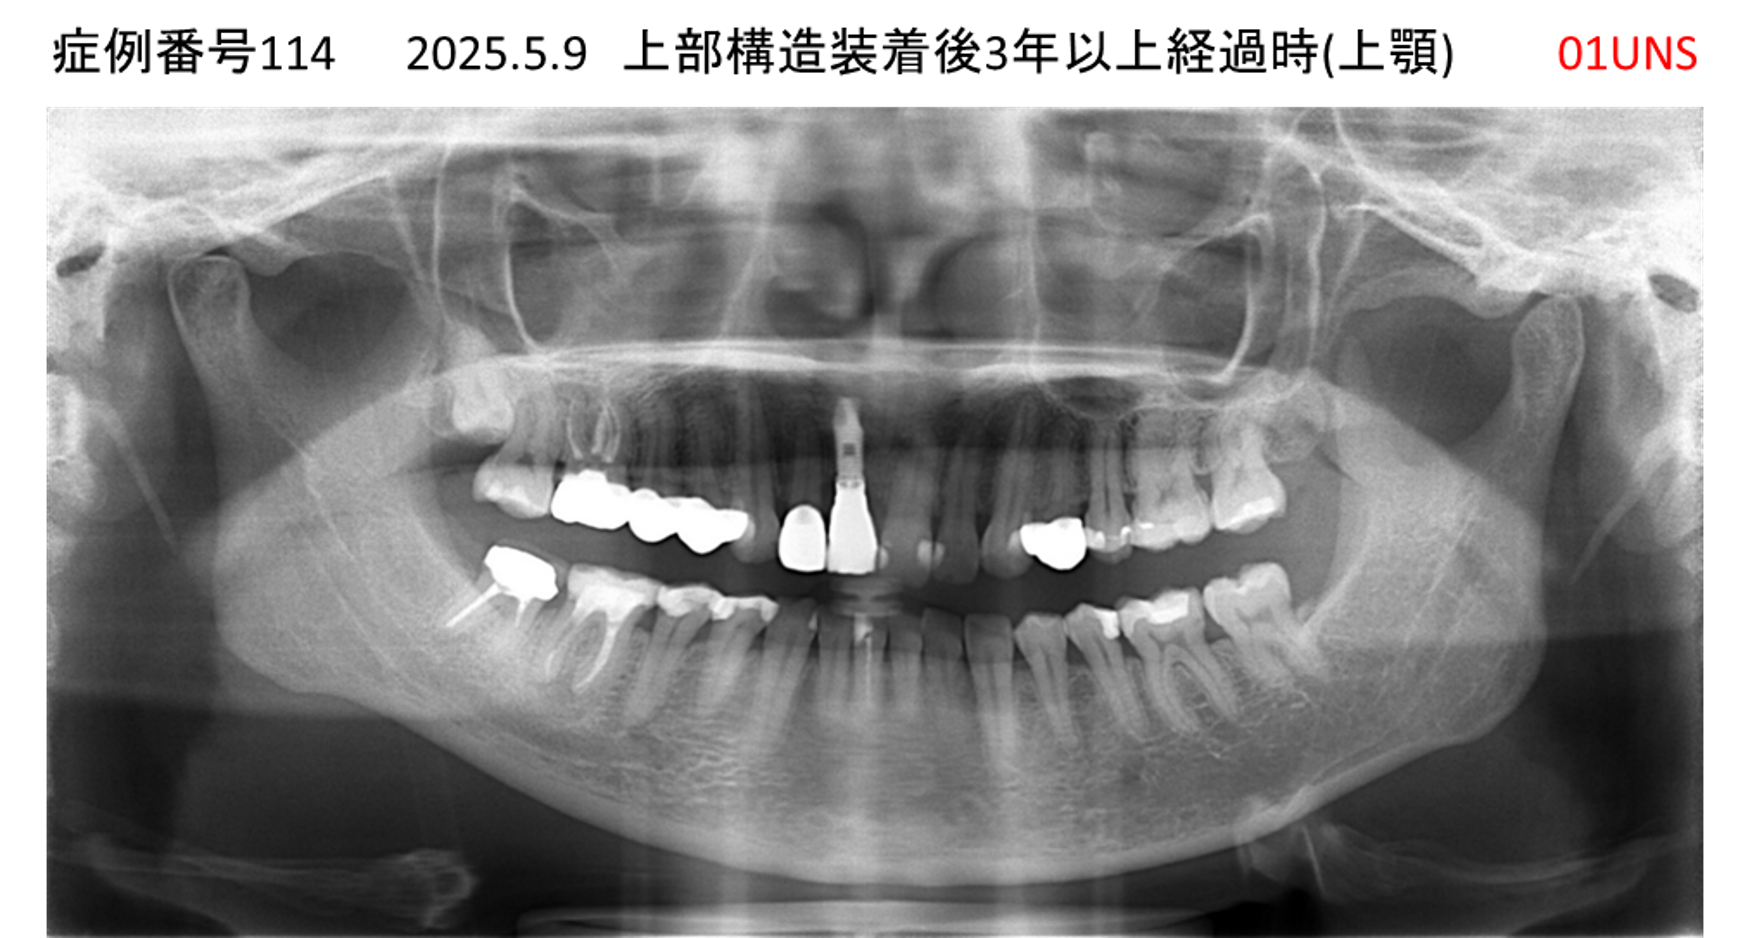

上の前歯が揺れてきてかめない患者様のインプラント症例

| 治療名称 |

インプラント |

| 治療費用 |

335万円+税 |

| 治療期間 |

4か月 |

| 患者さんの症状(主訴) |

上の前歯が揺れてきて噛めない |

| 治療内容 |

サイナスリフト 抜歯即時インプラント |

| 治療結果 |

ちゃんと噛めるようになった。不安がなくなった。見た目がとても良くなったのすごくうれしい。 |

| 治療の注意点(リスク/副作用) |

インプラントが壊れたら再治療が必要 |